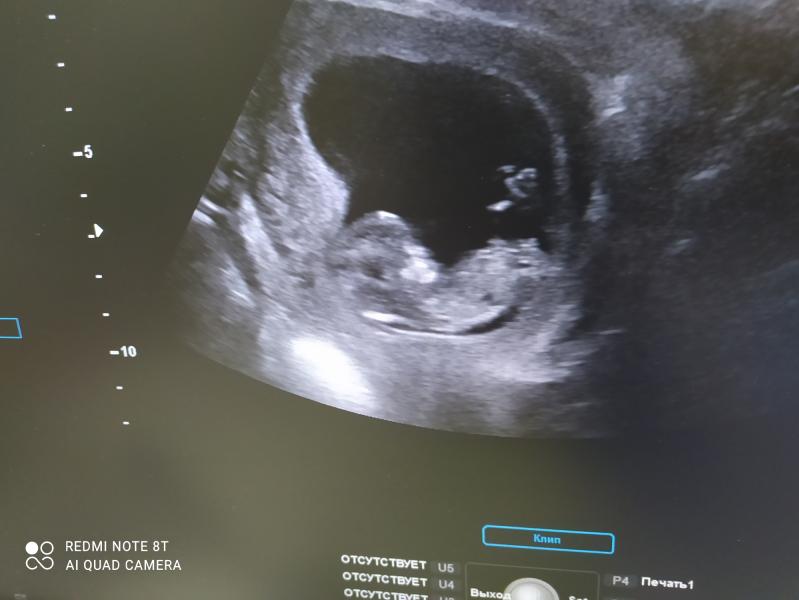

Мы были на узи слава богу все с малышем хорошо анализы отличные и малыш развивается хорошо. Девочки скажите кто нибудь на моем сроке слышал чсс через доплер? Хочу купить доплер но боюсь что ге услышу сердце. У кого был доплер на каком сроке нашли чсс?